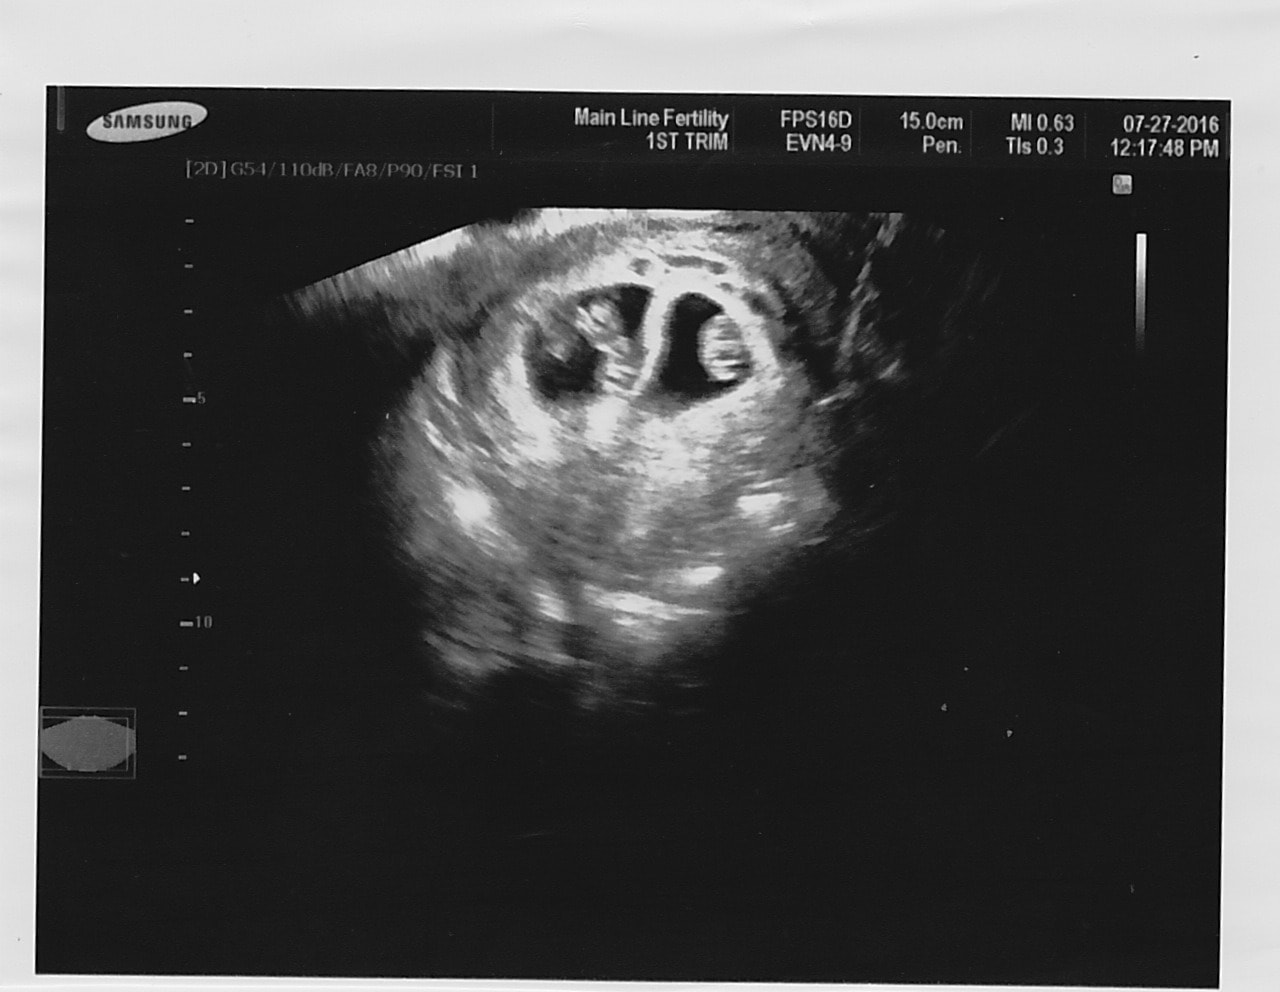

Ultrasound Photos of 9 Weeks Pregnant With Twins